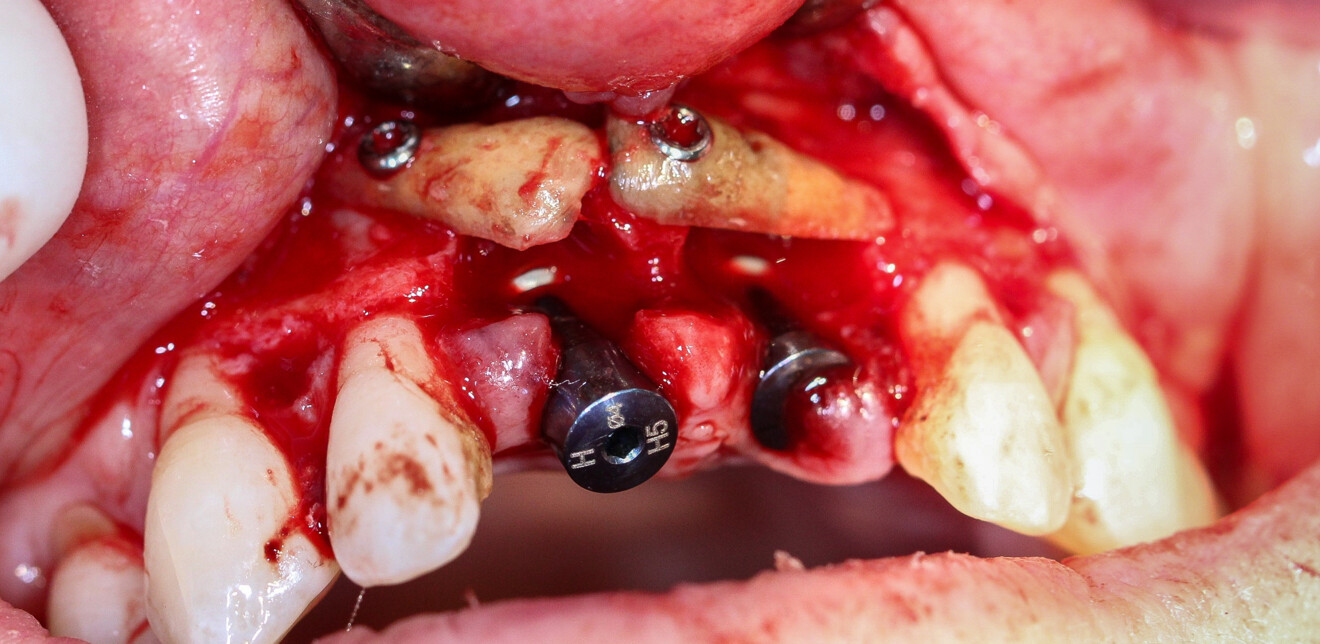

Nous réalisons un lambeau avec une incision crestale décalée en palatin en 11 et 21, sulculaire en 12, 13, 22, 23, en prenant soin de préserver les papilles interdentaires, ainsi que deux décharges verticales en distal des canines. Nous réalisons un décollement de pleine épaisseur (Figs. 28 et 29). Les dents (12, 22 et 18) sont facilement extraites et les alvéoles curetées avec soins. Deux implants (4*13) sont positionnés dans la paroi palatine des alvéoles, il subsiste une déhiscence vestibulaire en 22. Les racines de 12, 22 et 18 sont séparées dans le sens de la longueur. Les racines préparées comme indiqué ci-dessus, sont vissées en vestibulaire et en occlusal de la crête, au moyen de vis d’ostéosynthèse (diamètre 0,9 mm), afin de reconstruire la crête osseuse au niveau des inters de bridge ainsi que la paroi vestibulaire de la crête au niveau de 22 (Figs. 30 et 31). Le gap vestibulaire entre les implants et la crête ainsi que l’espace entre la crête et le greffon au niveau de 21, sont comblés avec un matériau d’origine synthétique (Collapat II Symatese). Le lambeau est tracté, suturé coronairement avec un fil tressé synthétique 5.0 (Fig. 32). Des piliers coniques droits pour prothèse plurale transvissée sont posés, et une empreinte prise à la fin de l’intervention (Fig. 33). Un provisoire est réalisé dans la journée par notre laboratoire de prothèse et posé le soir même. (Figs. 34 et 35)